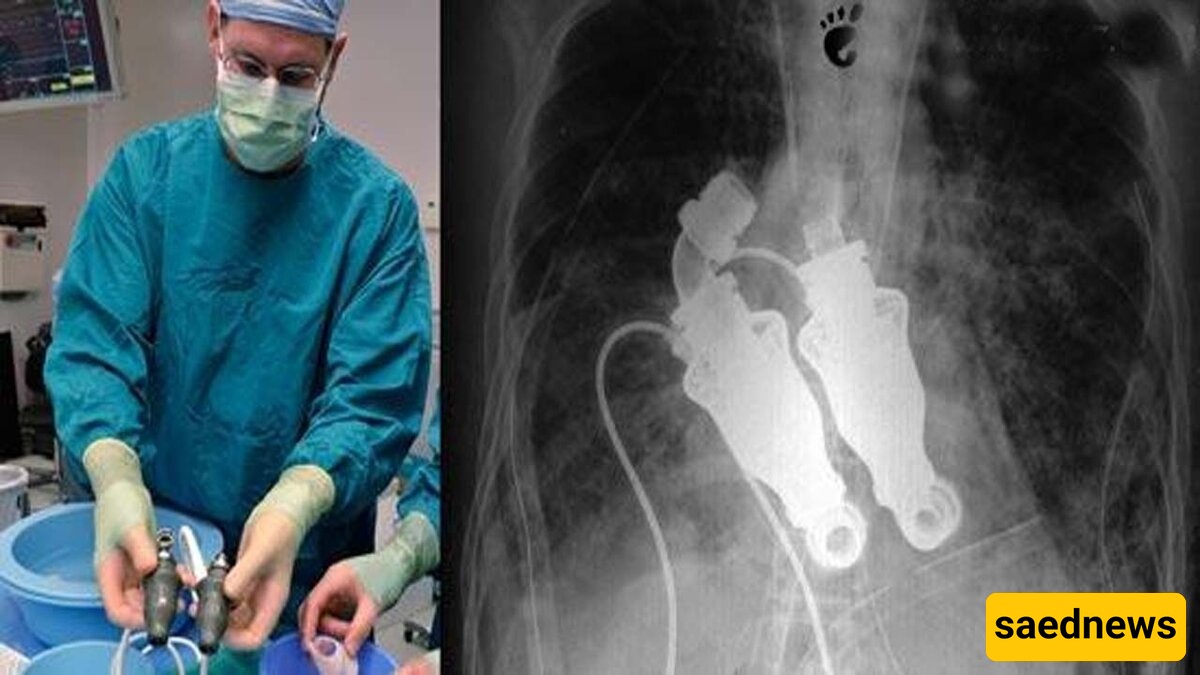

Dr. Billy Cohn and Dr. Bud Frazier suggested to Craig’s family that they remove his heart and implant a device that would circulate his blood without any heartbeat. Craig Lewis agreed, and this procedure kept him alive. The story was so remarkable that filmmaker Jeremy Zagar, a two-time Emmy nominee in 2010, documented the life of the first heartless human in full detail.

Drs. Cohn and Frazier had been working for years on a project called “Total Artificial Heart.” They tested their device on nearly 50 calves. Each time the device replaced a calf’s heart, the animal would stand up the next day and continue normal activities—eating, sleeping, moving, even running—despite having no heart to pump blood.

When these early trials proved successful, media attention surged. Dr. Cohn explained: “If you place a stethoscope on one of these calves, you hear no heartbeat. An ECG shows only a straight line. Yet, they are alive, and blood circulates through their veins.”

Craig Lewis’s condition worsened daily, leaving doctors increasingly anxious. He was only a short time from death. After hearing Drs. Cohn and Frazier’s proposal, Craig’s family had to make a swift decision. In March 2011, his wife agreed, allowing the doctors to remove his heart and implant the device.